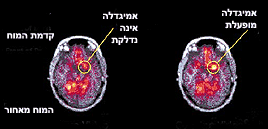

בתמונה משמאל: מוחו של מכור לקוקאין, לאחר תקופה של ניקיון, צופה בסרט טבע ותוך כדי כך נעשית הדמיה מוחית. בצילום מודגש אזור ה'אמיגדלה' - והוא אינו פעיל.

בשלב מסוים מראים למכור סרט על שימוש בקוקאין. התוצאה בתמונה מימין: אזור ה'אמיגדלה' מתחיל להיות פעיל, 'נדלק', והמכור מדווחו על תחושה של כמיהה לסם.

המסקנה: רמזים מהסביבה המזכירים את הסם יכולים לעורר תגובה מוחית (הגברת פעילות באזור מוגדר - ה'אמיגדלה'), והביטוי הרגשי של התגובה הזו יהיה תחושה של כמיהה לסם.

האיור המופיע כאן ממחיש היטב למה הכוונה: במהלך מחקר התבקש נבדק שנגמל מקוקאין לצפות בסרטים בעודו עובר הדמיה מוחית. בעוד הנבדק צופה בסרטים, עקבו החוקרים אחר אזור במוחו הנקרא 'אמיגדלה' (Amygdala). כשהנבדק צפה בסרט טבע תמים, האמיגדלה לא היתה פעילה. אולם כשהחלו להקרין לנרקומן לשעבר סרט על שימוש בקוקאין - 'נדלקה' האמיגדלה (ראו תמונה) והמכור החל לדווח על כמיהה לסם. לפיכך הסיקו החוקרים שרמזים מהסביבה שמקבל המכור שנגמל המזכירים לו את הסם, עלולים לעורר אצלו תגובה מוחית שהביטוי הרגשי שלה יהיה כמיהה מחודשת לסם. "מכאן הסקנו שיסוד ההתמכרות הוא ביולוגי, אך עוצמת ההתמכרות והנטייה להתמכר שונים מאדם לאדם", מסביר ד"ר הרמן.